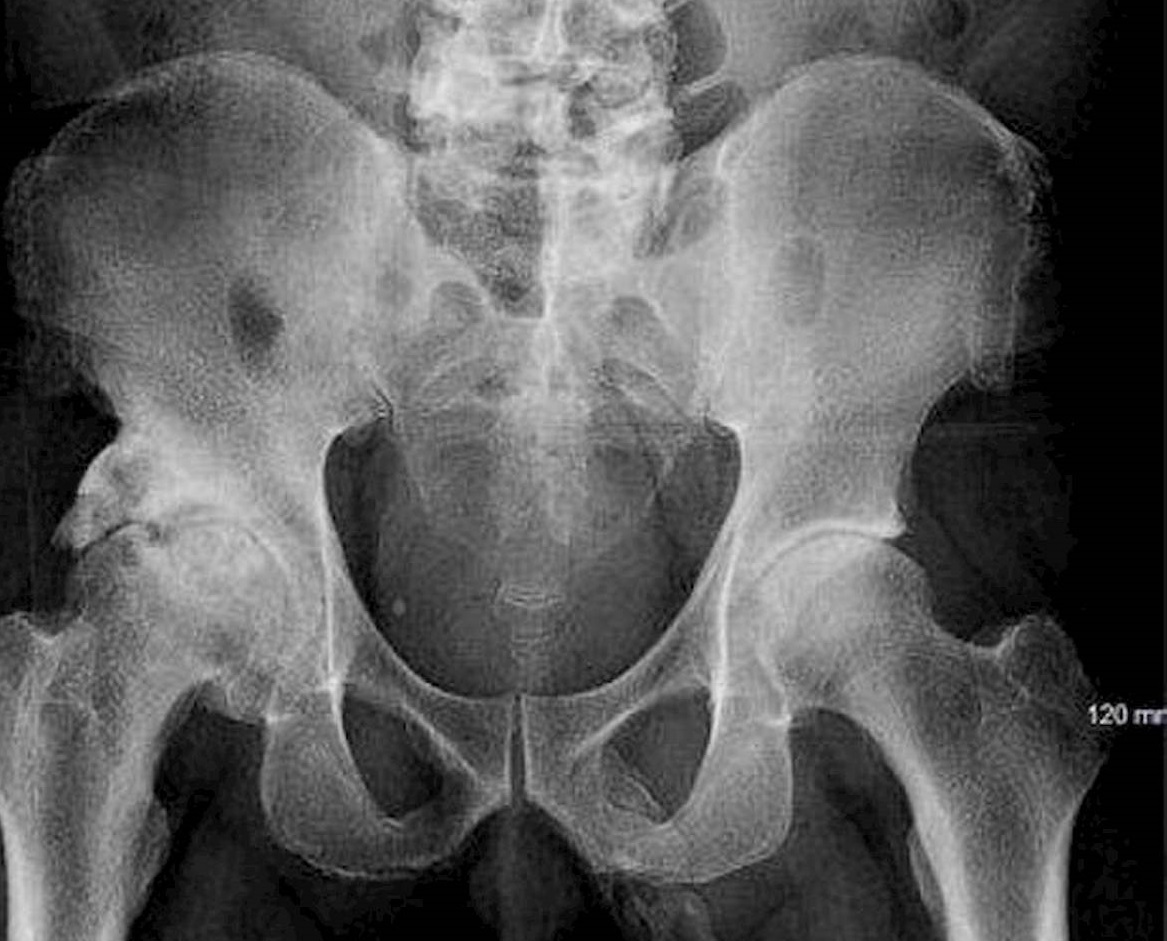

La radiografia del 63enne

Dalla radiografia non era emersa alcuna frattura al bacino ma i medici del Lincoln Medical and Mental Health Center, avevano rilevato qualcosa di strano: all’interno dell’organo se****le si stavano formando delle cellule ossee, una patologia chiamata ossificazione del pene. Georges El Hasbani dell’American University of Beirut, spiega che è una condizione estremamente rara, che può essere una diretta conseguenza della malattia di Peyronie, dal chirurgo francese che l’ha scoperta, un’anomalia anatomica del pene dovuta alla formazione di tessuto fibroso-cicatriziale che può portare anche all’incurvamento dell’organo.